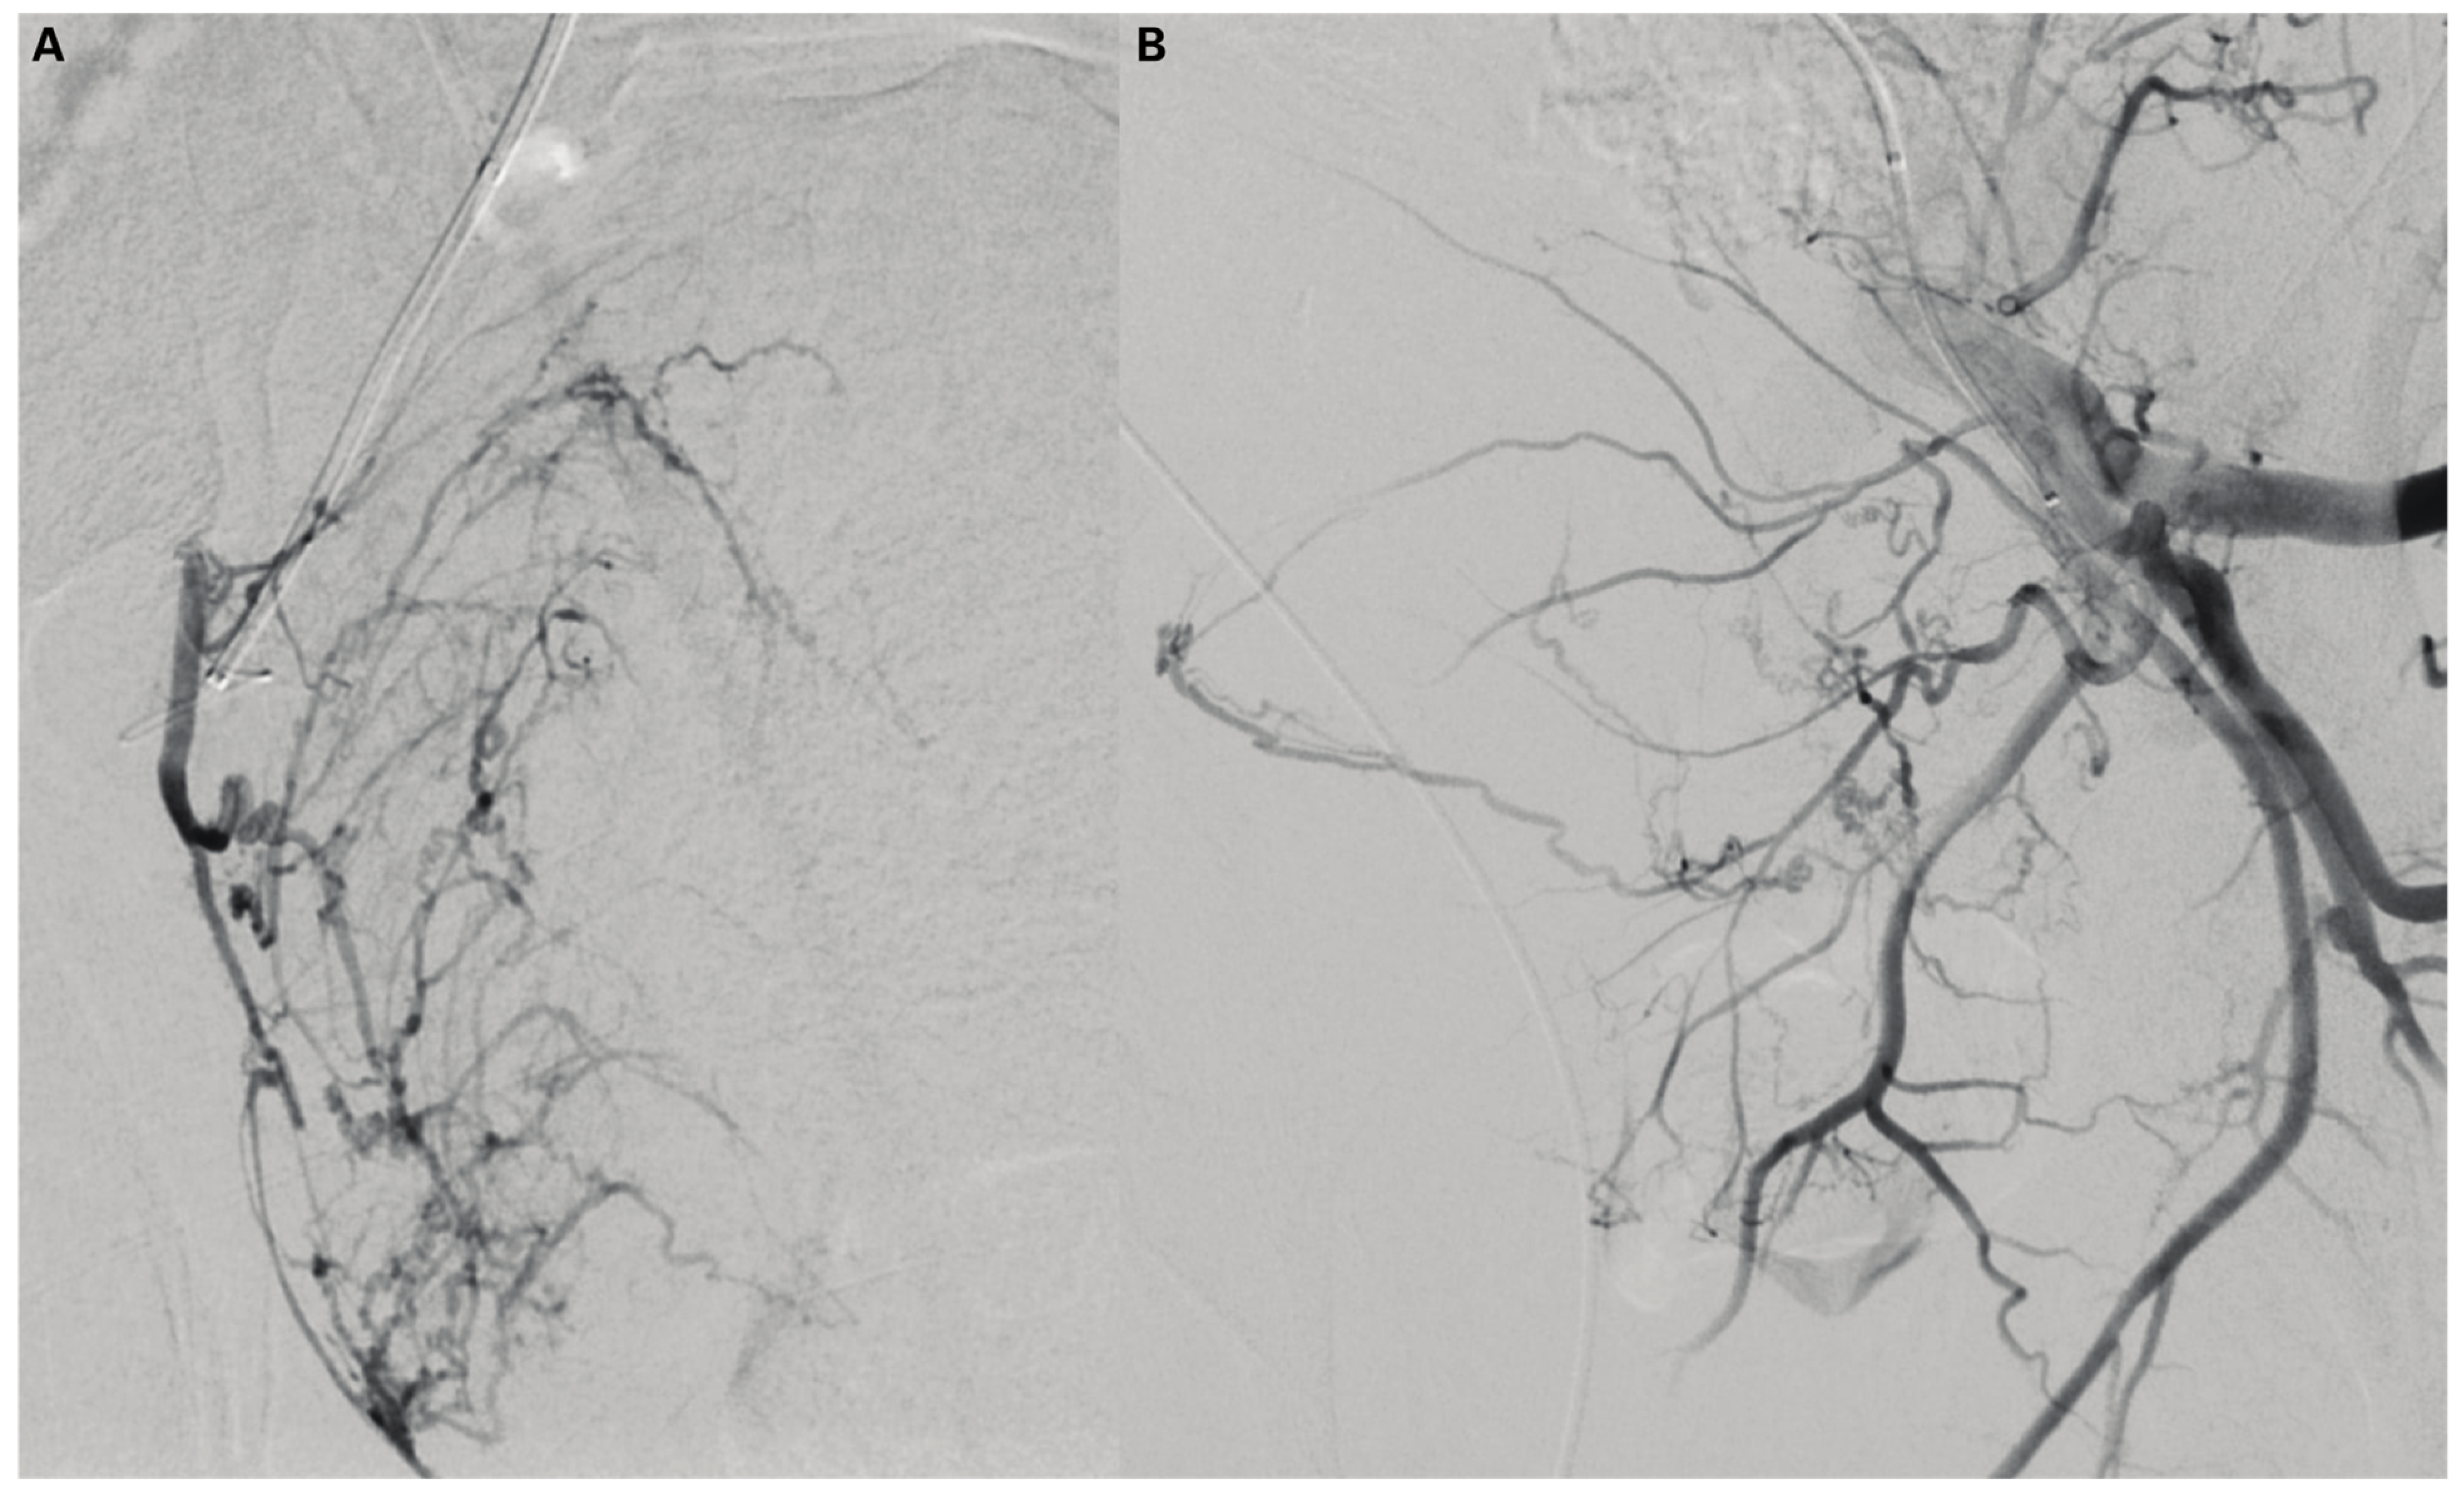

Prostate Artery Embolisation of Megaprostate Causing External Iliac Vein Compression